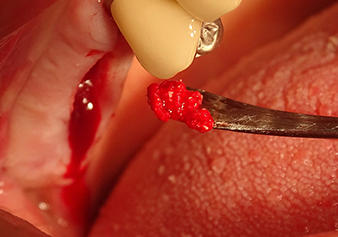

Implant bed preparation and augmentation

Following an intermediate check (Fig. 4) a further preparation step was performed (Fig. 5). Afterwards, the hydraulic Z35P instrument was used to lift the membrane to the desired position (Fig. 6 and 7). This was followed by further piezosurgical preparation of the implant bed, concluded with a rotary bur and shoulder milling cutter up to the implant diameter of 4.8 mm. Before the implant was inserted, the augmentation material (particle size approx. 0.8-1.6 mm) was introduced underneath the Schneiderian membrane (Fig. 8).

A periosteal elevator is used to place an augmentative mixture carefully into the region of the internal maxillary sinus ostium in the apical direction

Fig.8: A periosteal elevator is used to place an augmentative mixture carefully into the region of the internal maxillary sinus ostium in the apical direction.